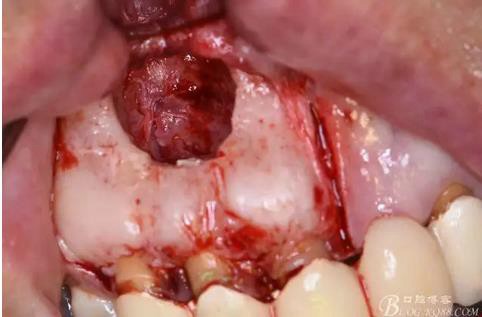

圖11.摘除囊壁后形成的骨腔

圖12.超生骨刀切除12根尖